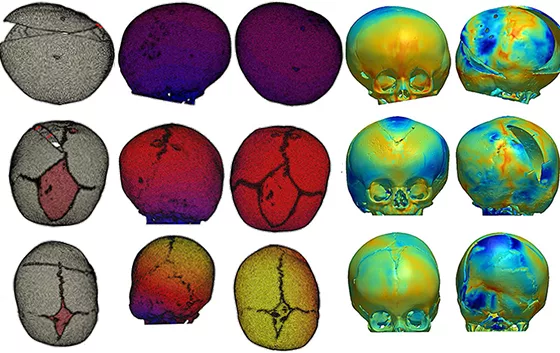

3 例因颅骨形态异常的 LC 患者在英国伦敦大奥蒙德街医院颅颌面外科接受了弹簧辅助颅成形术,并在术前和术后进行头部 CT 扫描。将 CT 图像导入 Simpleware ScanIP 软件中重建这两个不同阶段的颅骨,经过分割和处理以确定颅骨至上颌骨及骨缝结构的骨骼。

在 Simpleware FE 中采用结构化的 3D 四面体单元生成颅骨的有限元(FE)模型,对不同的解剖区域赋予合适的材料属性建模。在对颅骨模型进行截骨之前,通过使用热膨胀系数在 MSC Marc 中近似模拟术前成像和手术之间的颅骨生长。将颅内体积(ICV)作为表示不同阶段颅骨大小的参数,包括在 Simpleware ScanIP 中通过选择颅顶内表面进行术前CT重建。

重建的颅骨模型展示了术前 CT 时的颅内腔形态,对三名患者的模拟结果进行对比。FE 模型和从 CT 获得术后颅骨模型的分析显示额骨和颞骨的表面偏差率相对较低,在被弹簧扩张的后颅骨上表面偏差增大。